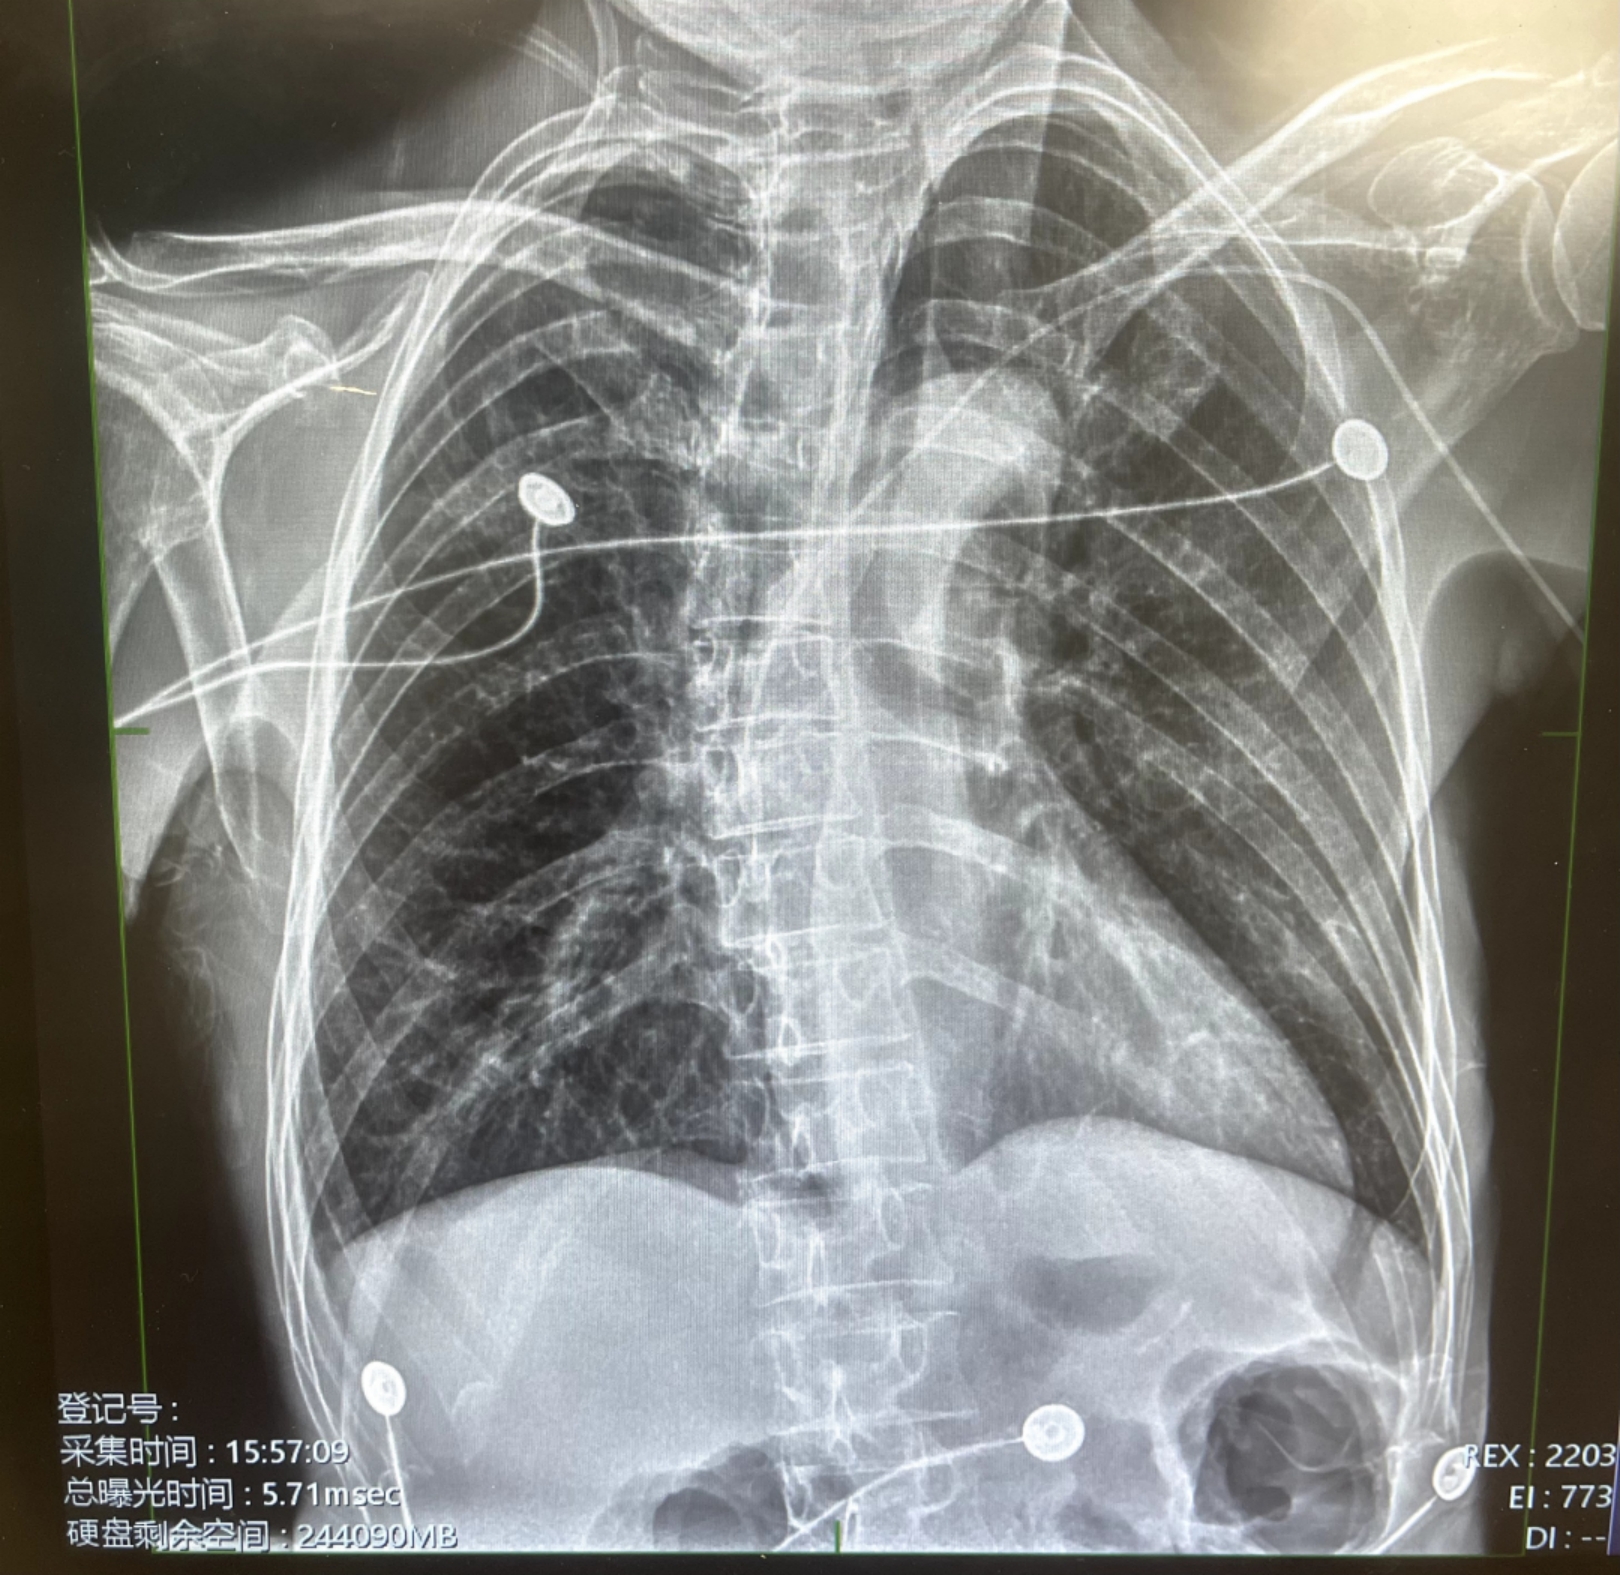

这是我院第一例PICC置管术,此次PICC置管技术难度较高,但在医院最强技术后盾支持下,肿瘤专科护士喻莉翠主动请缨,在刘国涛护士长的指导配合下,经患者贵要静脉穿刺,超声引导下成功送入导丝,导管送至预定刻度,封管贴膜固定,一气呵成顺利完成我院第一例PICC置管术。放射科医师床旁胸片复核中心静脉置管位置准确无误。整个操作过程非常顺利,患者无任何不适,连连称赞我们的医护人员技术好、态度好、服务好。